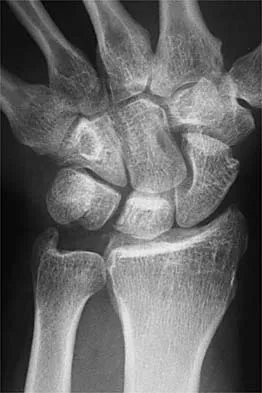

A 19-year-old woman fell onto her nondominant hand 6 weeks ago. Radiographs are shown in Figures 37a and 37b. A decision has been made to treat this fracture surgically. What is the best approach to treat this fracture?

Explanation

Displaced fractures of the scaphoid are best treated with compression screw fixation. Proximal third fractures (as in this patient) are optimally approached via a dorsal approach to ensure proper reduction and compression. Fractures of the scaphoid waist can be approached either by a volar or a dorsal approach. Kirschner wire fixation is limited to proximal pole fractures that are too small to accommodate the trailing head of a compression screw. Retting ME, Raskin KB: Retrograde compression screw fixation of acute proximal pole fractures. J Hand Surg Am 1999;24:1206-1210.